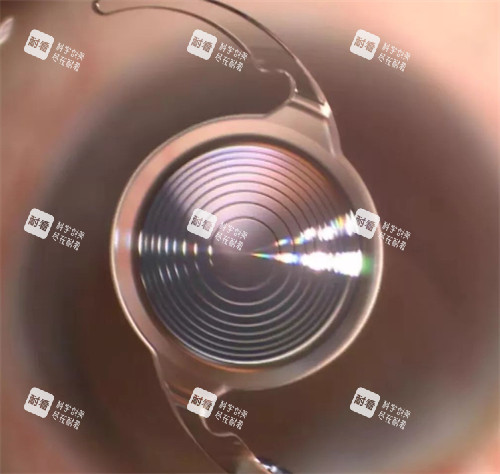

人工晶状体选择:人工晶状体是白内障手术中重要的耗材,其种类繁多,价格差异也较大。

有国产的普通人工晶状体,价格相对较低;也有进口的高端人工晶状体,具备更好的光学性能和视觉质量,价格则会高一些。

患者可以根据自己的经济状况和眼部情况选择合适的人工晶状体。

超声乳化白内障手术是利用超声波将混浊的晶状体粉碎并吸出,然后植入人工晶状体。

它的切口小,术后修复快,对患者的眼部损伤较小,能够更快地修复视力。